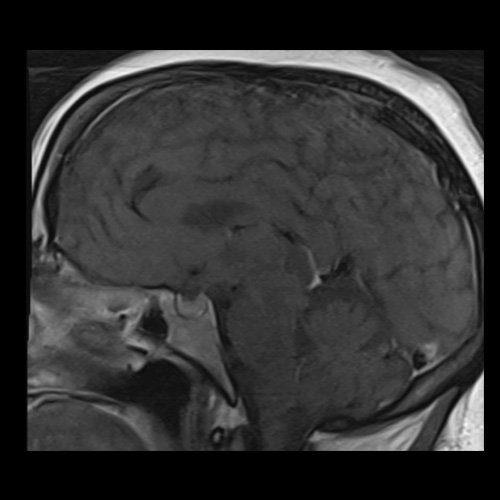

RMN de cráneo con contraste endovenoso (21/02/26) Corte sagital en secuencia T1: sin alteraciones en región selar.

RMN de cráneo con contraste endovenoso (21/02/26) Corte coronal en secuencia T1: sin alteraciones en región selar.

RMI de cráneo con contraste EV (21/02/26): Las cavidades ventriculares presentan tamaño y morfología normal. Las estructuras la línea media se hallan en su topografía habitual. A nivel de la fosa posterior el cuarto ventrículo se encuentra en línea media. Bulbo, protuberancia y mesencéfalo sin alteraciones. Relación sustancia gris blanca respetada. No se observan efectos expansivos. El examen de difusión no muestra alteraciones. El efecto FLAIR no muestra alteraciones. La secuencia SWI no muestra alteraciones. No se visualizan alteraciones en proyección, de la región selar, el quiasma óptico y senos cavernosos. No se observan realces patológicos tras la administración de gadolinio.